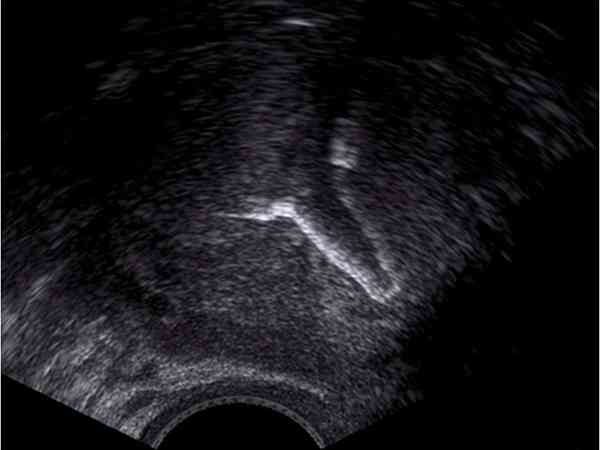

爱母环是以子宫活动力学原理为设计路线研制而成的一种具有抗排斥功能、优质长效、副反应轻微的宫内节育器。其长相如下:

- 2. 根据子宫形态及力学原理设计,两臂特定张角、呈完全开放V形,支架有柔弱的弹力可随子宫的缩舒而收张;

- 4. 支架两臂端的铜粒,由于被放置在近两侧子宫角处的关隘位置在此处形成铜离子高浓度区,充分发挥了铜离子的避孕作用;